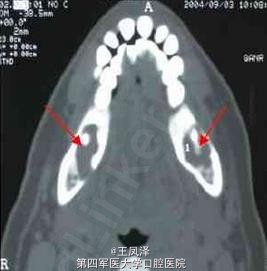

上、下颌骨囊肿CT诊断学

患者女性,49 岁。主诉:右侧后下牙痛近1 年。CT 下颌骨轴扫示:双下颌骨体部齿源性囊肿。术后病理证实。